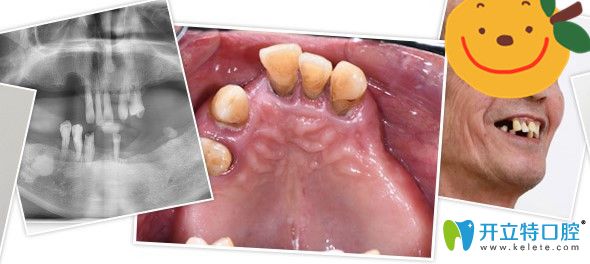

▼郭老全口種植牙前后對比照

侯國鎮(zhèn)為郭老做全口種植牙前后對比照

▼沒有做種植牙前

沒有來廣州廣大口腔做種植牙前

其實郭老之前剛?cè)毖赖臅r候做過活動假牙,但是因為異物感強烈,并不怎么佩戴,因為脫落牙齒周邊沒有支撐,慢慢的,他的牙齒都逐漸脫落松動,到他決定做種植牙前,他全口只剩上面5顆牙,下面4顆牙和一顆殘根,而且全都松動的很厲害,吃東西嚼不爛,非常痛苦。

牙齒情況:全口僅剩9顆牙和一顆殘根